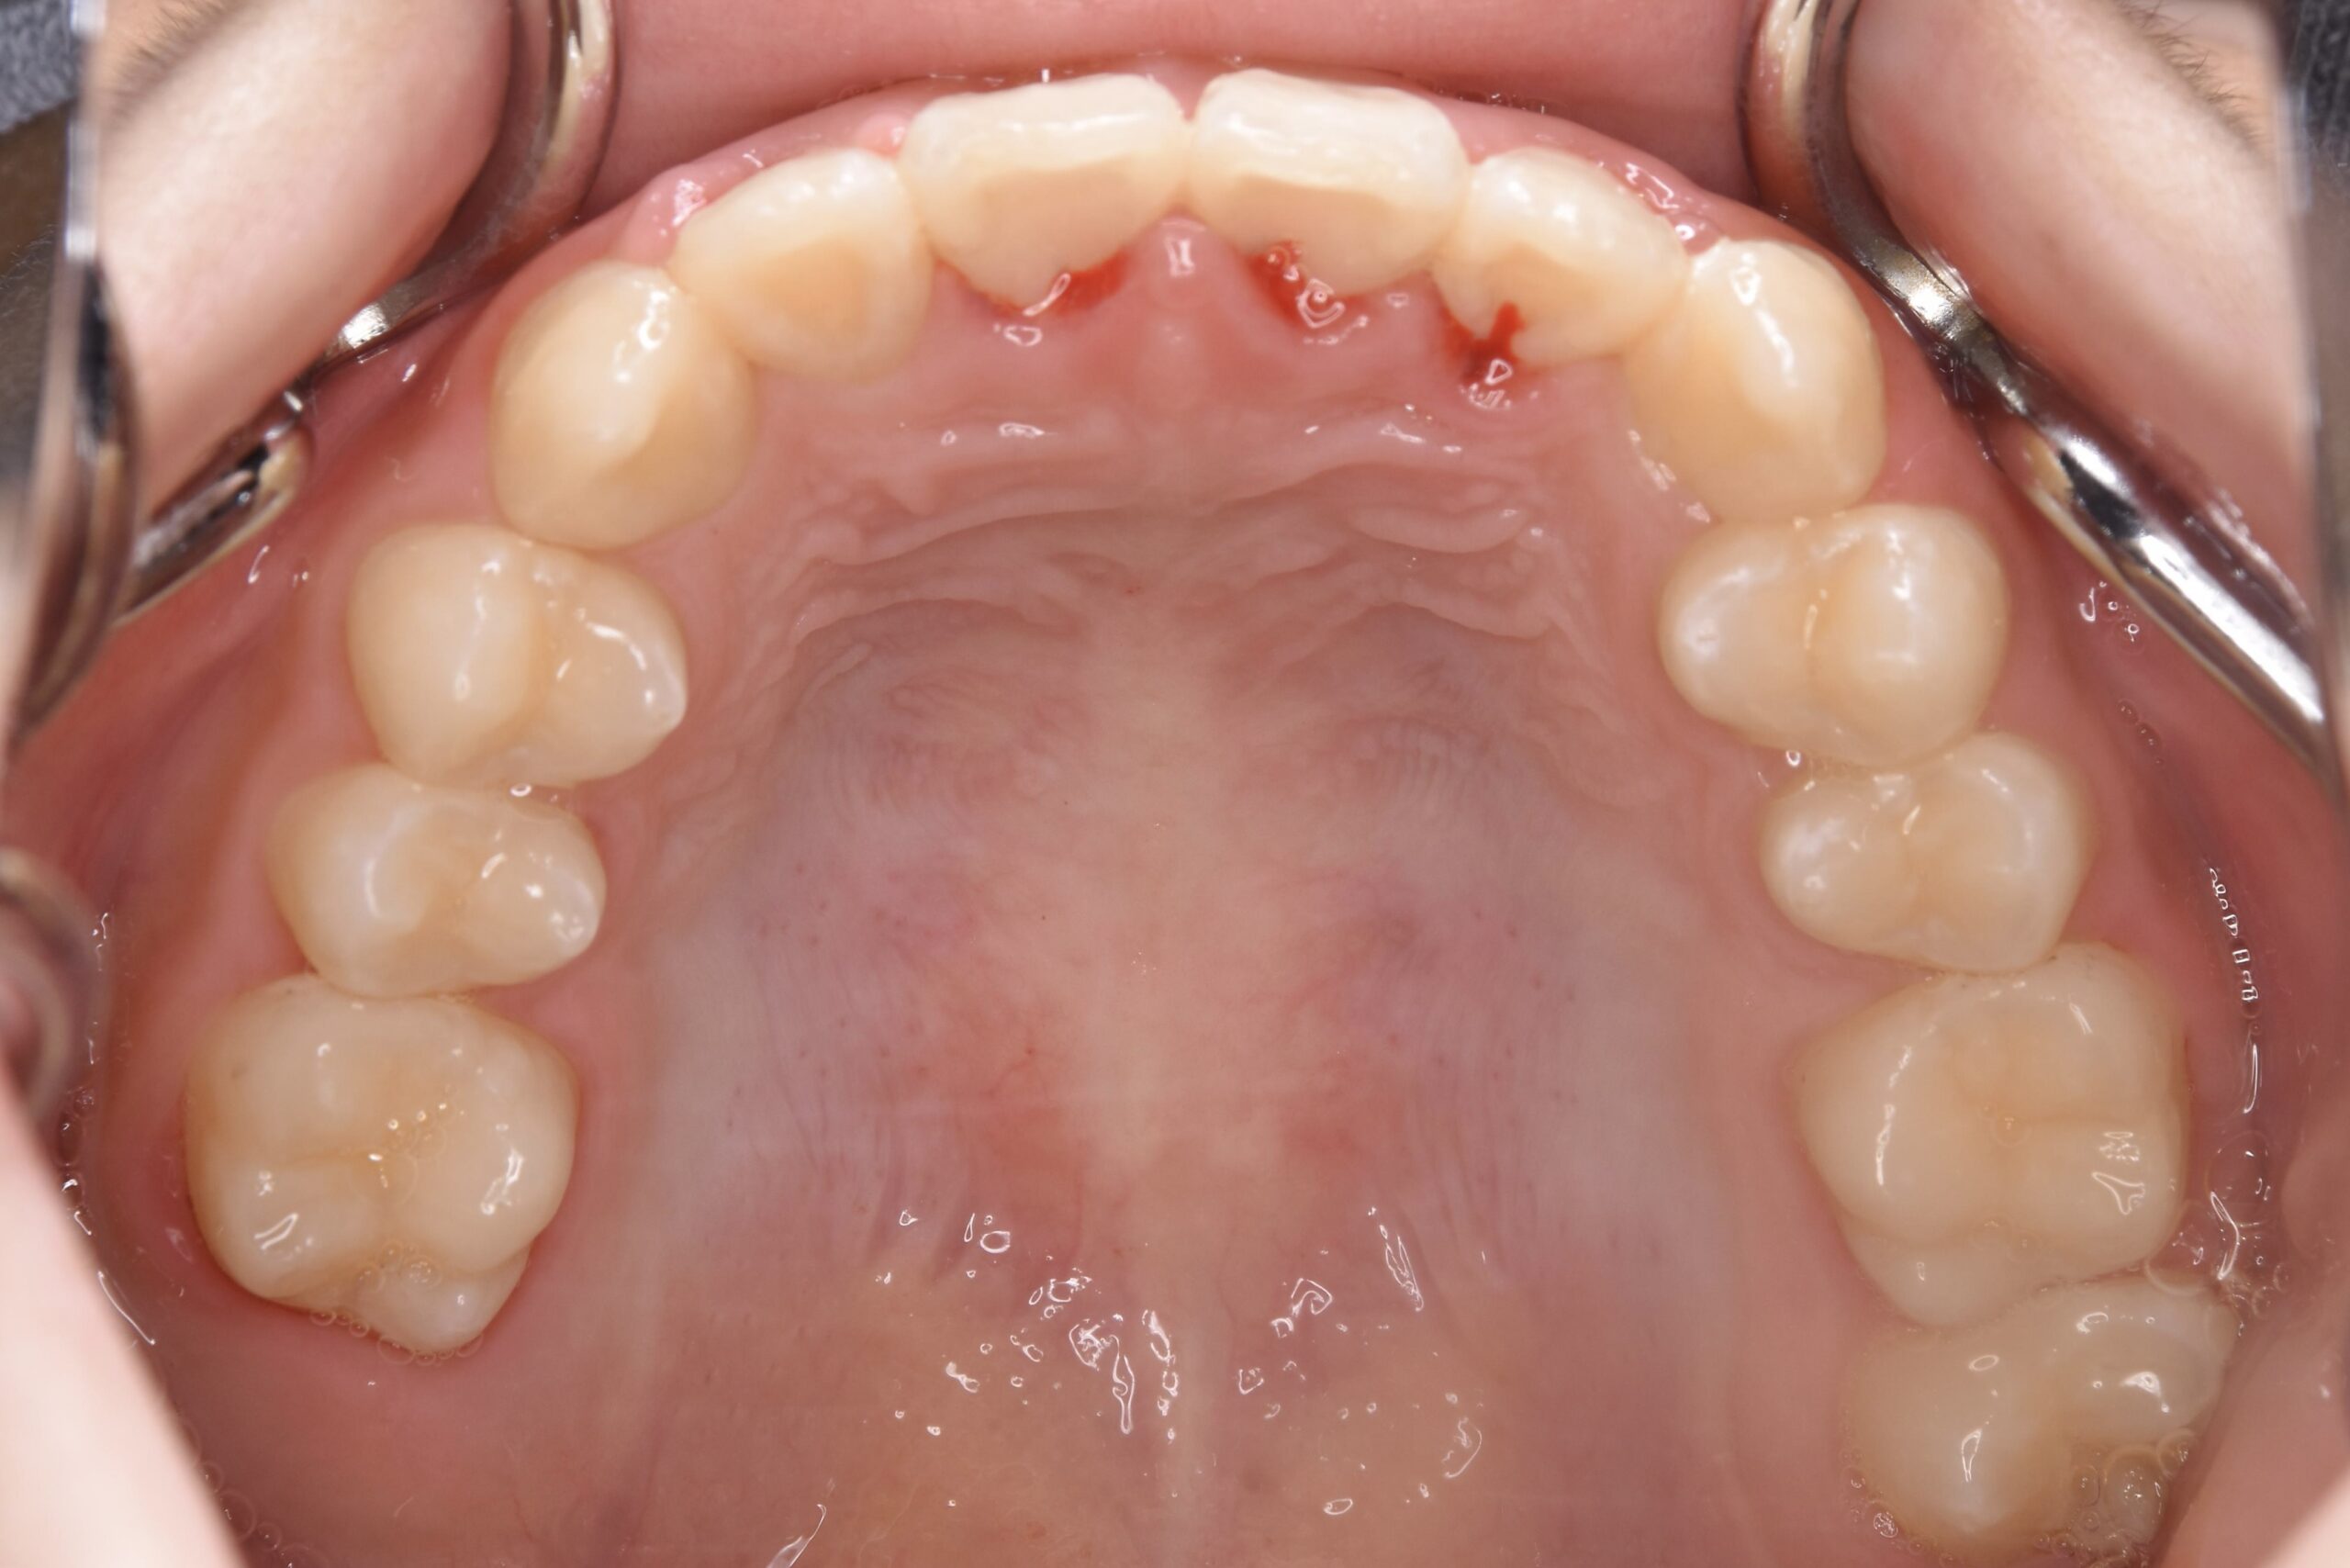

AFTER

診断名・主な症状 下顎前歯の叢生を伴う過蓋咬合

治療内容 上下の歯並びの幅を拡げつつ、前歯の関係を改善しました。

抜歯部位 抜歯なし

治療期間 2年 + 後戻り止め期間(3年 )